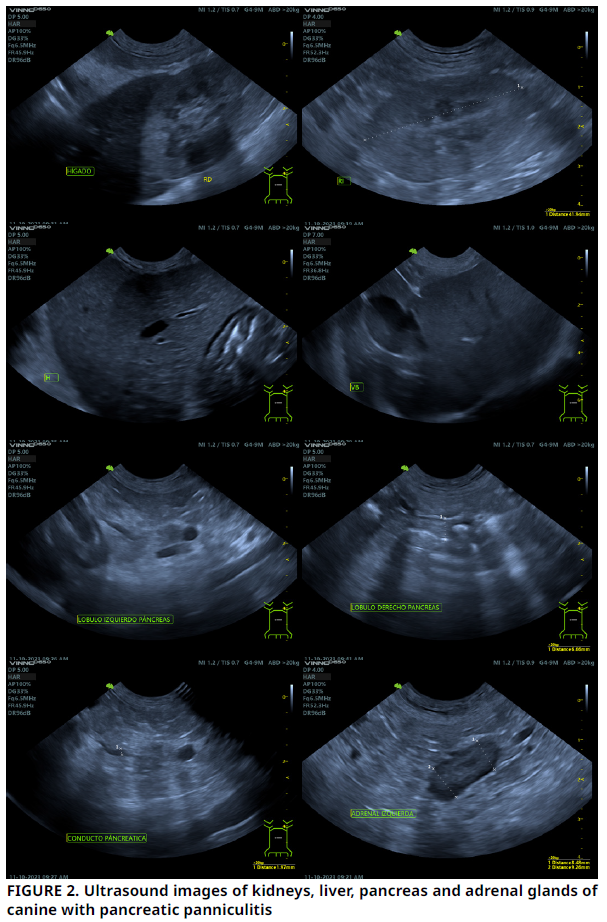

Medicina Veterinaria - Reporte de Caso